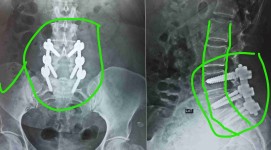

تزحزح بالفقرات القطنية مع ضيق بالقناة العصبية قبل وبعد الجراحة

توسيع ضيق بالقناة العصبية القطنية مع تثبيت الفقرات

ضيق بالقناة العصبية القطنية مستويات متعددة مع تزحزح فقاري قبل وبعد الجراحة